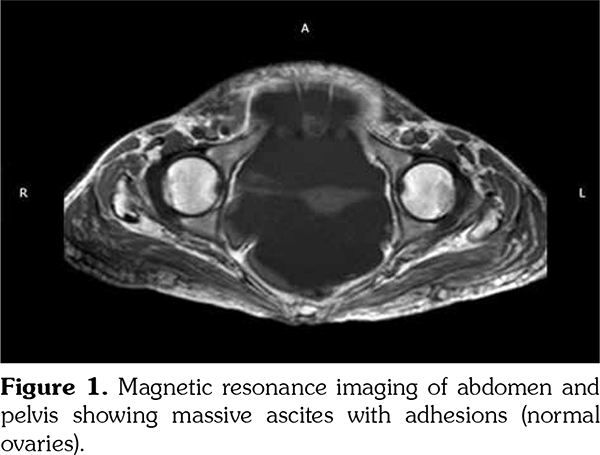

We performed extended investigations that showed normal blood albumin level. Tumor markers were significant only for an elevated serum cancer antigen 125 (CA-125) (80 U/L normal <35). Work-up for TB was negative including adenosine deaminase and polymerase chain reaction in ascitic sampling. Cytology was negative for malignant cells. We conducted computed tomography scan for the chest, abdomen and pelvis with contrast showing massive ascites with ill-defined omental thickening related to the anterior abdominal wall. A cystic lesion was seen at perineal region, minimal bilateral pleural effusion and massive abdominal ascites. Laparotomy and biopsy were performed revealing fat necrosis. Subsequently, magnetic resonance imaging of the abdomen and pelvis was conducted but it was insignificant apart from massive ascites with adhesions. No ovarian masses were observed (Figure 1). In lower perineal region, herniating peritoneal sac was noted containing ascitic fluid representing peritoneocele (Figure 2).